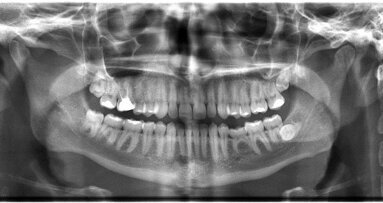

GÖTEBORG - Een röntgenopname van de kaak kan voorspellen of een patiënt een verhoogd risico loopt op fracturen in de rest van het lichaam. ...